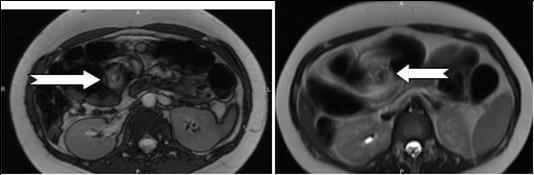

Figure 2A.Axial contrast-enhanced MRI scans show characteristic whirpool appearance of bowel and mesentery wrapping around superior mesenteric artery

Figure 2B.Axial contrast-enhanced MRI scans show characteristic whirpool appearance of bowel and mesentery wrapping around superior mesenteric artery

In that aspect, small bowel volvulus should always remain in the differential diagnosis in front of a pregnant woman presenting with abdominal pain during pregnancy, especially one like ours that was known for a previous surgery for appendicitis (a possible reason for the presence of the adhesions). Radiologic diagnosis of small bowel volvulus can be done by several technics. Plain abdominal film can be used, showing sometimes a typical pattern of dilated loops, but more often showing a normal radiological pattern due to a proximal position of the volvulus (with the loops being filled with liquid). Evidences on CT-scan are the presence of dilated bowel loops, intramural gas and the “whirlpool sign” (Cong et al, 2014; Shui et al, 2011)4, 12, but the use of technics exposing the foetus to radiations is debated. However, in their review, Cong et al 4emphasized the fact that those technics (and particularly plain radiography) are considered safe for the mother as well as for the foetus (Cong et al, 2014)4. MRI is also safe and extremely precise in the diagnosis of small bowel obstruction (Vassiliou et al, 2012)13, sometimes also showing the “whirlpool sign” (Kouki et al, 2013)7 and ultrasonography has been reported to be useful in some instances (Cong et al, 2014)4 but it can also remain completely negative. In our case, while cholangio-MRI suggested the diagnosis, final diagnosis was given by intestinal MRI, showing a possible role for this technic in some unusual cases, in which doubts about the diagnosis or about the state of different abdominal structures remain. However, in cases in which clinical symptoms, laboratory and more basic radiological (plain abdominal film of CT-scan) are highly suggestive of this pathology, exploratory surgery should be started at the earliest time possible.